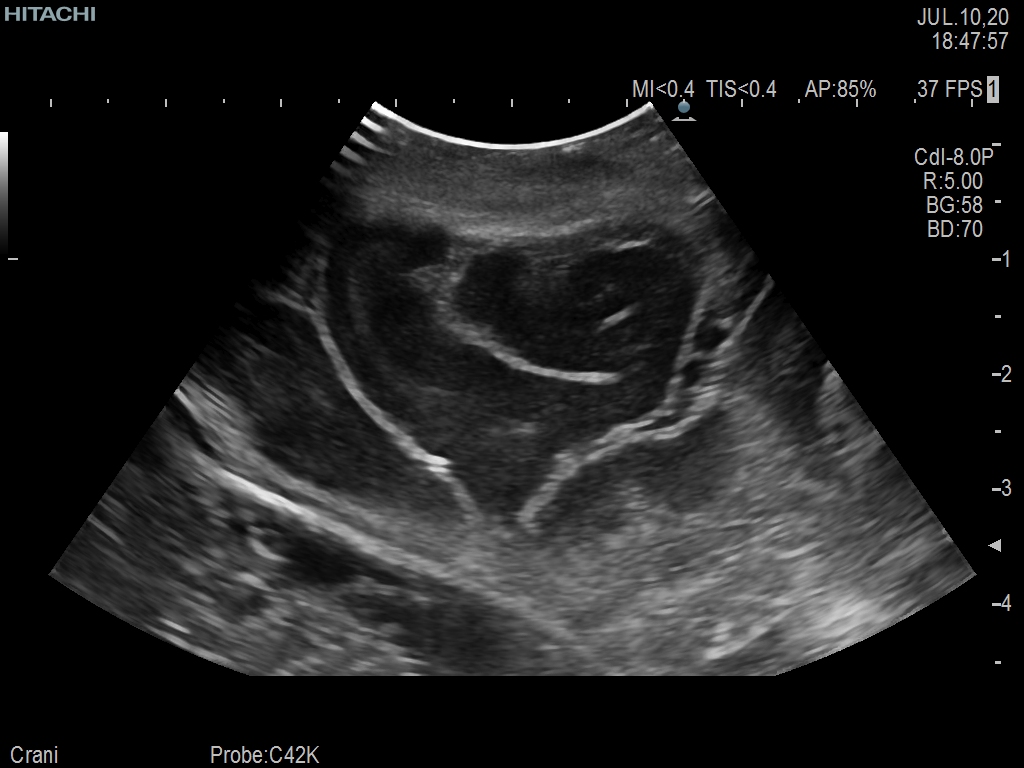

Superior guidance for all applications

Fujifilm Healthcare Americas is committed to designing tools that help surgeons navigate inside the human body and provide the necessary information to immediately make critical surgical decisions.

Fujifilm Healthcare's dedication to Surgeons provides outstanding ultrasound technology, professional support and the specialized tools necessary to best perform comprehensive real-time ultrasound imaging in Breast Surgery, General Surgery, Laparoscopic Surgery, Neurosurgery, Robotic Surgery and Surgical Oncology.

Recognized for our outstanding image quality, outstanding system reliability and intuitive use of cutting edge technology, Fujifilm Healthcare remains the standard in the field of Surgery.

Recognized for our outstanding image quality, outstanding system reliability and intuitive use of cutting edge technology, Fujifilm Healthcare remains the standard in the field of Surgery.